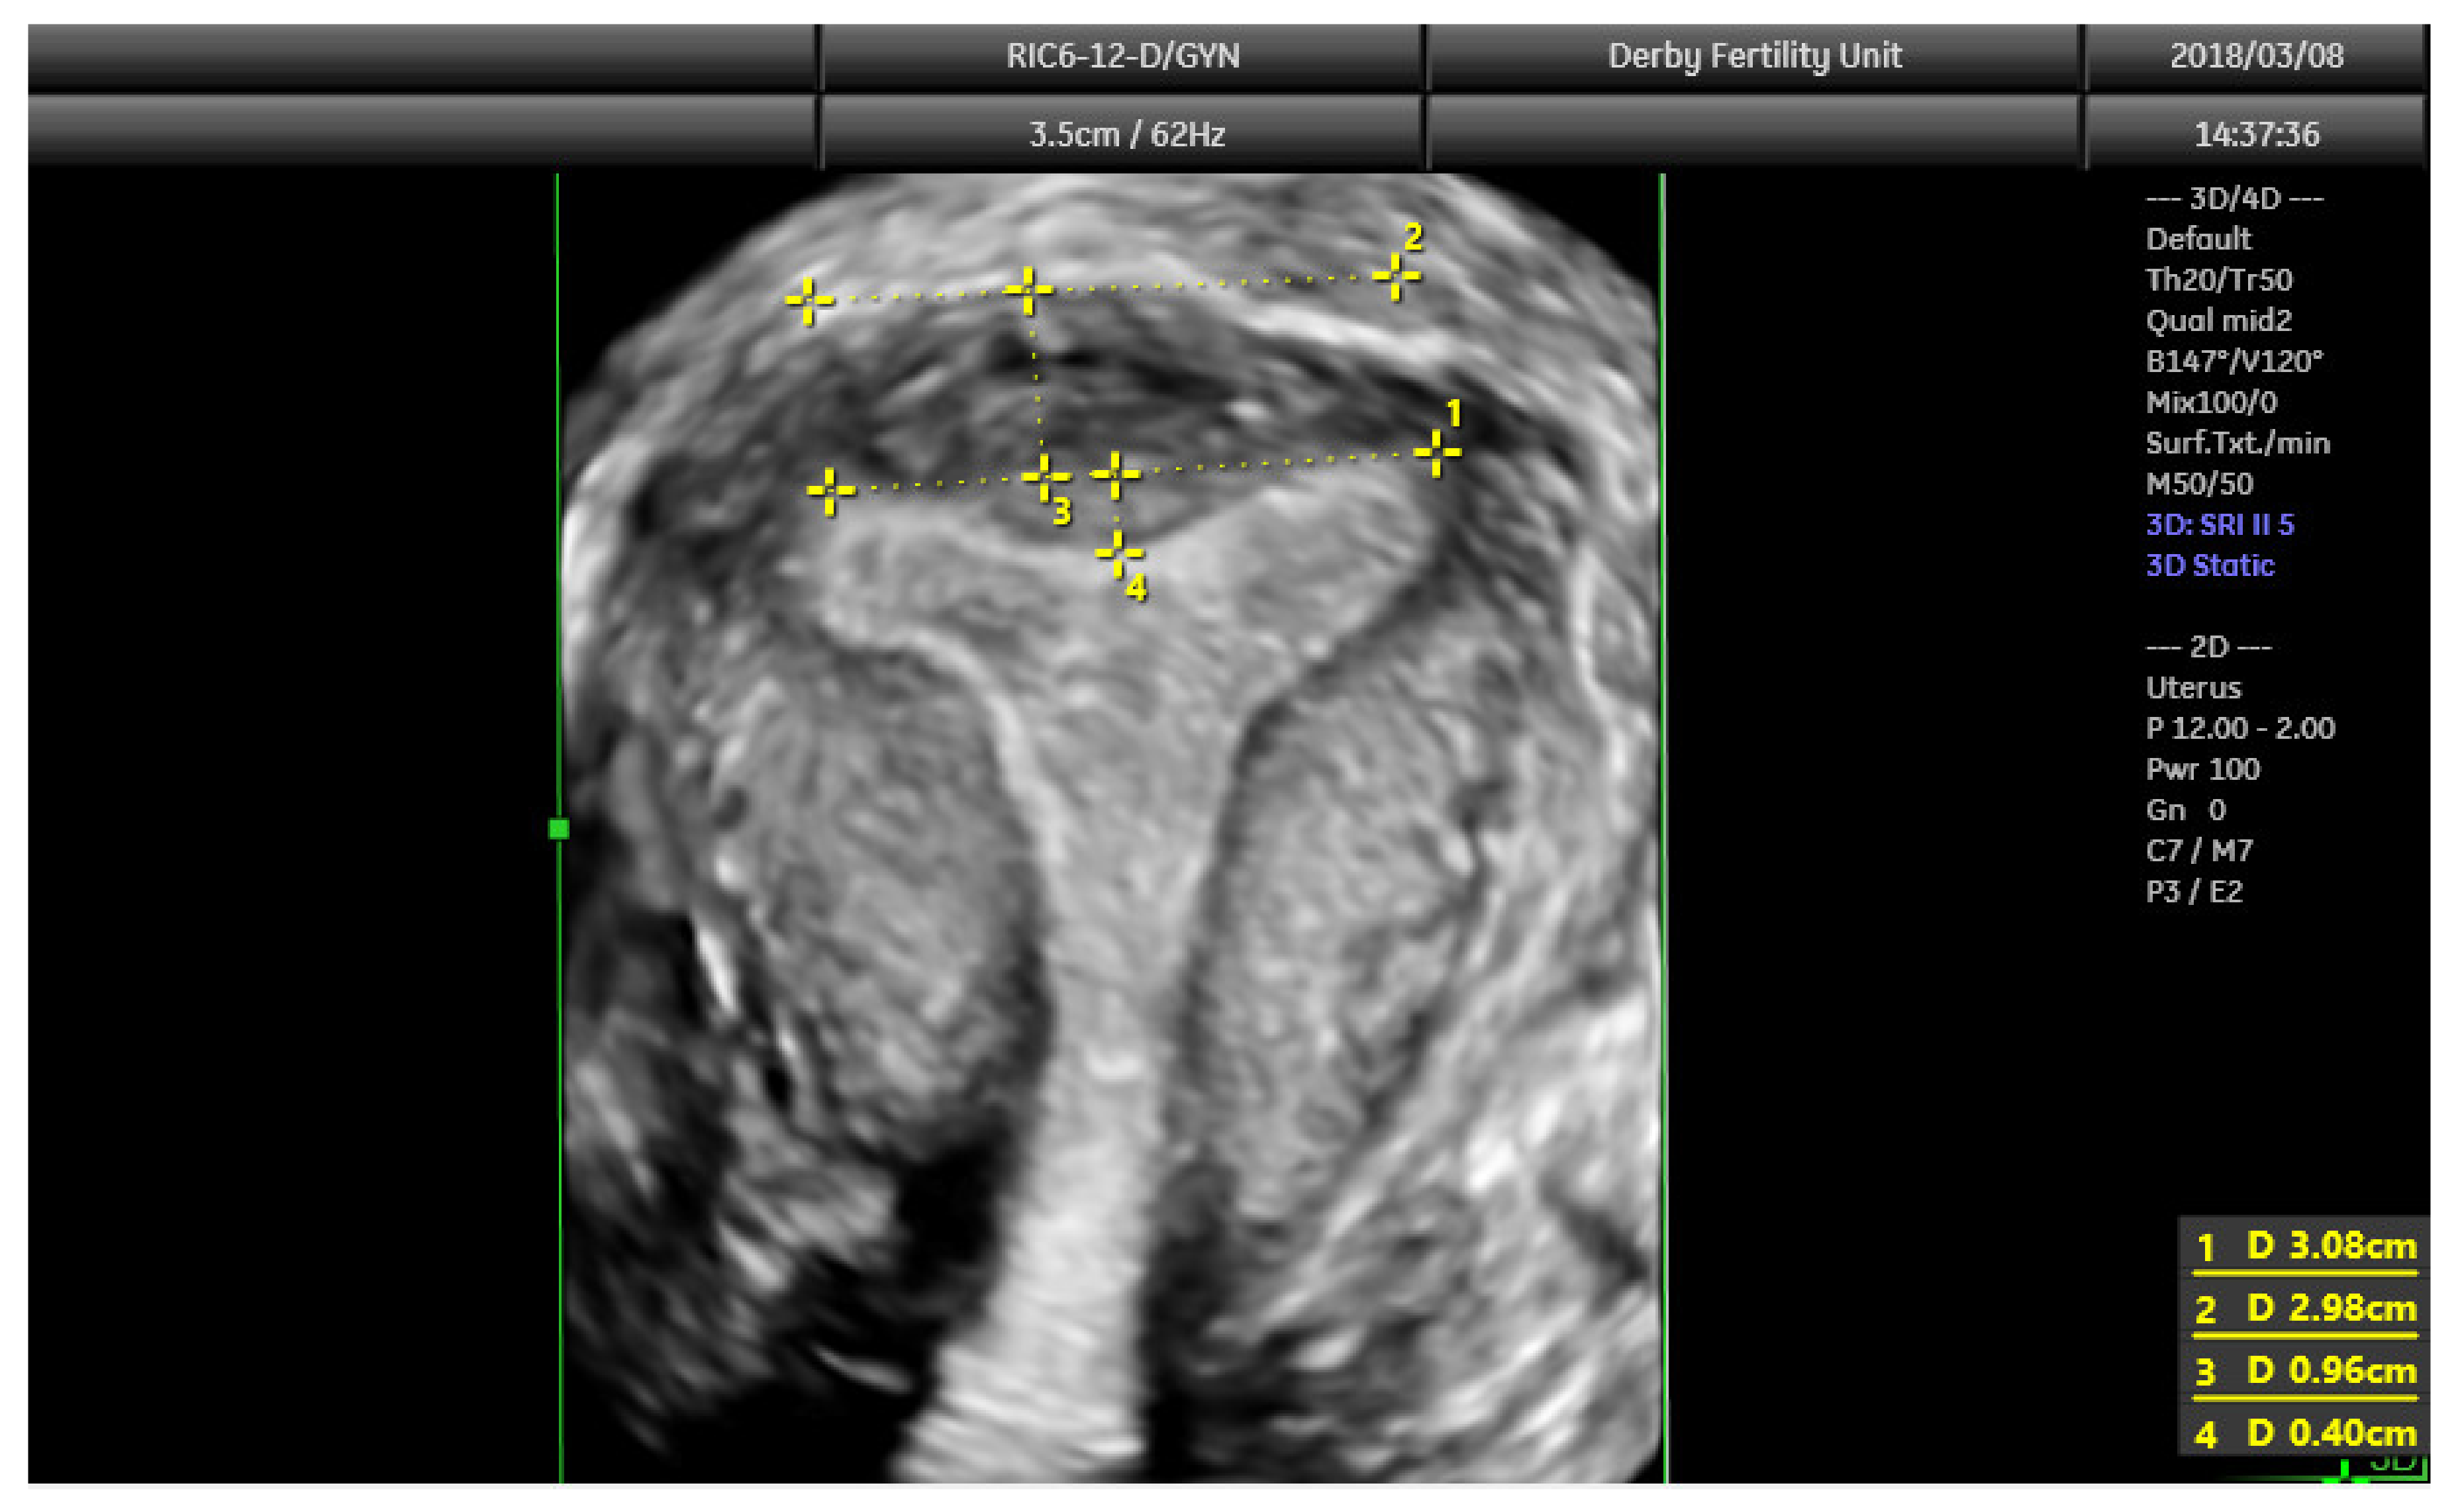

The diagnostic accuracy of 3D ultrasound compared with laparoscopy ± hysteroscopy in diagnosing CUA is highest among other imaging modalities including MRI. The diagnostic accuracy of 3D ultrasound is reported as 97.6% with sensitivity and specificity of 98.3% and 99.4%, respectively [18]. The morphology of the uterus is best examined in the coronal plane (Figure 8) using the interstitial portions of the fallopian tubes as reference points. A line joining the tubal ostia (interostial line) is the reference line (Figure 9). A parallel line on top of the fundus can be drawn and the vertical distance between this line and the interostial line is the uterine wall thickness. In cases of septate uterus, a parallel line along the apex of the internal midline indentation is drawn and its vertical distance from the interostial line is the septal length. The vertical distance between the parallel line along the bottom (apex) of the external indentation and interostial line is the depth of the external cleft in cases of partial bicorporeal (bicornuate) uterus.

Figure 9. 3D coronal plane of uterus with assessments: interostial line (measurement 1); a parallel line along the serosal surface (measurement 2); uterine wall thickness (measurement 3) and septal indentation length. This uterus is not septate, but may be classified as arcuate uterus, which has no clinical relevance based on the recent ESHRE and ASRM guidelines.